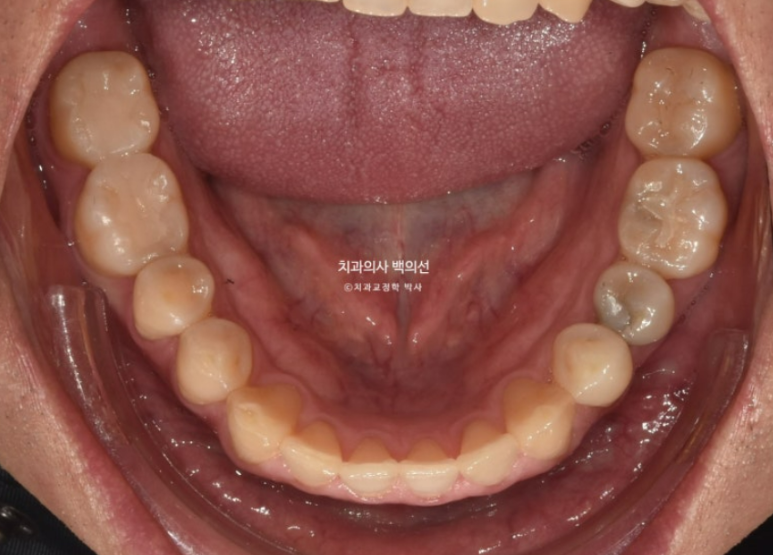

어금니 교합은 좋고

25.03

유지장치까지 붙은 모습입니다.

교정 후 파노라마 엑스레이상 치근흡수는 없으며 치근형행도는 좋습니다.